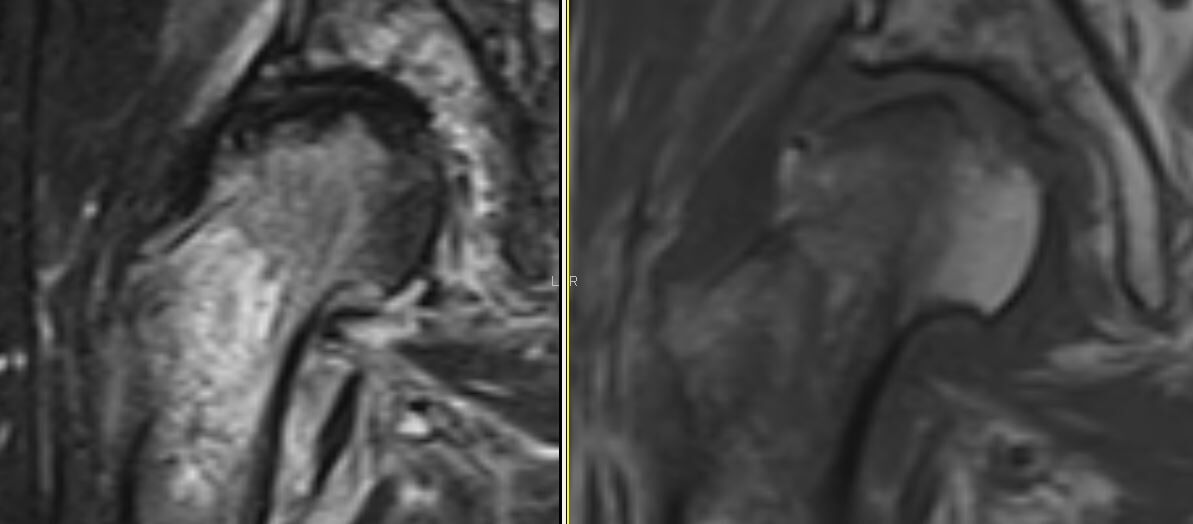

発症後2週間のMRIが上記です。大腿骨頚部から転子部にかけて、T1WIで低信号領域、T2WIで高信号領域を広範に認めます。

大腿骨頚部にわずかに骨折線がありそうですが判然としません。大腿骨頭荷重部直下にT1WI、T2WIとも低信号を認めます。最初は大腿骨頭下脆弱性骨折と診断しました。